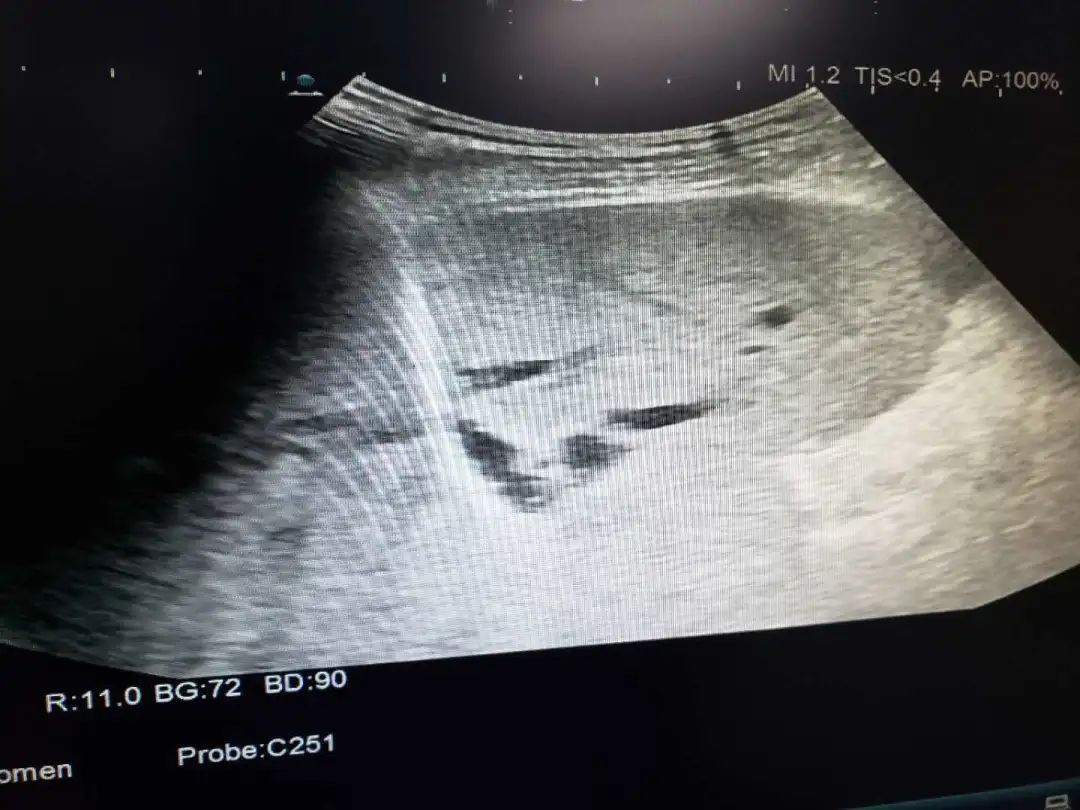

诊断是治疗的前提,正确的诊断,相当于成功了一半,活检则是确诊的唯一金标准。超声介入活检适用于全身各部位软组织的活检,如淋巴结、甲状腺、乳腺等。

适用于肝囊肿、肾囊肿、甲状腺囊肿等囊性病变。在超声引导下,用一根细针,直接经皮肤进入囊肿内,抽尽囊液,注入特殊药物,拔出细针便能治好。整个治疗过程仅需30-60分钟,经过数月,囊肿慢慢吸收。

具有定位准确、操作安全的优势。适用于肺肝脓肿、肾脓肿、盆腔脓肿的引流,以及胸腔、腹腔积液的引流。